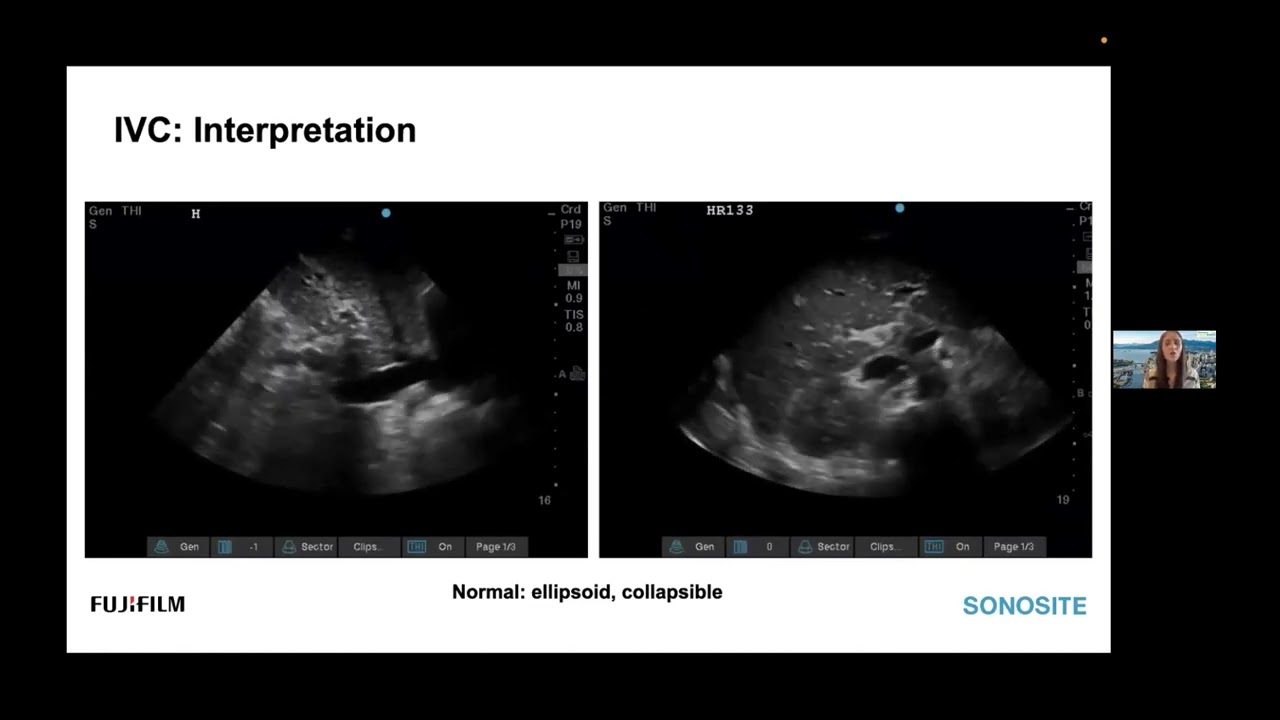

Point-of-care ultrasound is often compartmentalised such that the clinician will focus on one body system while performing a critical care ultrasound examination. Instead of this compartmentalised approach, VExUS allows you to evaluate for venous congestion using point-of-care Ultrasound and can be performed when trying to assess the fluid status of the patient.

The VExUS Score can give you evidence of venous congestion in the liver, gut and kidneys to help predict early signs of end-organ damage and allow you to change/optimise your fluid management approach for your patient.